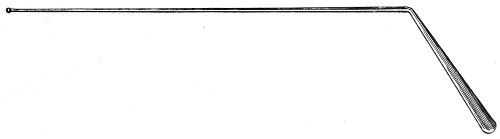

The uterine sound is an instrument by which the length of the uterine cavity may be determined (Fig. 15). The sound, which is a large surgical probe, somewhat curved to adapt itself to the normal shape of the uterine axis, is made of pliable metal, so that the curvature may be changed readily to suit any case. The sound is graduated, and at a position of 2½ inches from the tip is a small elevation marking the length of the normal uterine cavity.

Fig. 15.—Uterine sound.

The uterine sound was at one time used a great deal to determine the length and direction of the uterus, and 35 perhaps to assist in determining the character of the uterine contents or of the endometrium. With our present methods of examination, however, the sound is of but little if any use. The size and direction of the uterus can in nearly all cases be determined by bimanual examination. The use of the uterine sound is by no means free from danger. Many cases of septic endometritis and salpingitis have been caused by it, and the physician has often unintentionally committed an abortion by passing the sound in a pregnant woman. The uterine sound should never be used in a routine way. It should never be used unless one expects to determine with it something that cannot be determined by simpler methods of examination.

The most thorough aseptic precautions should be observed when the sound is introduced. The vulva, vagina, and cervix should be cleaned and the sound should be sterilized. The sound should never be introduced if there is any suspicion of pregnancy.